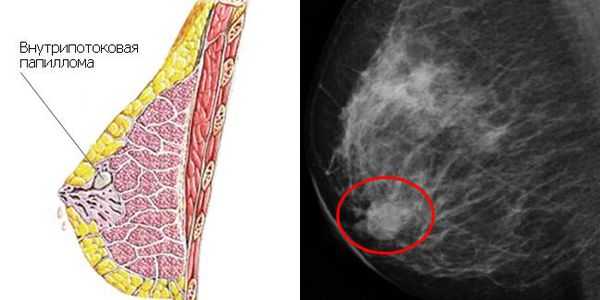

- в двух случаях (1 %) обнаружена внутрипротоковая папиллома;

- в четырёх случаях (2 %) — злокачественные образования, в том числе два случая (1 %) с инвазивным протоковым раком (возраст 22 и 31 год) и два случая (1 %) с лобулярной карциномой — предраковым поражением долек молочной железы (возраст 21 и 35 лет);

- с учётом внутрипротоковой папилломы как предракового состояния, общая частота злокачественных образований достигла 3 %.

Таким образом, макромастия может рассматриваться как фактор риска злокачественных новообразований молочной железы. По этой причине после проведения операции по уменьшению или удалению груди крайне важно проводить гистопатологическое исследование [12] .